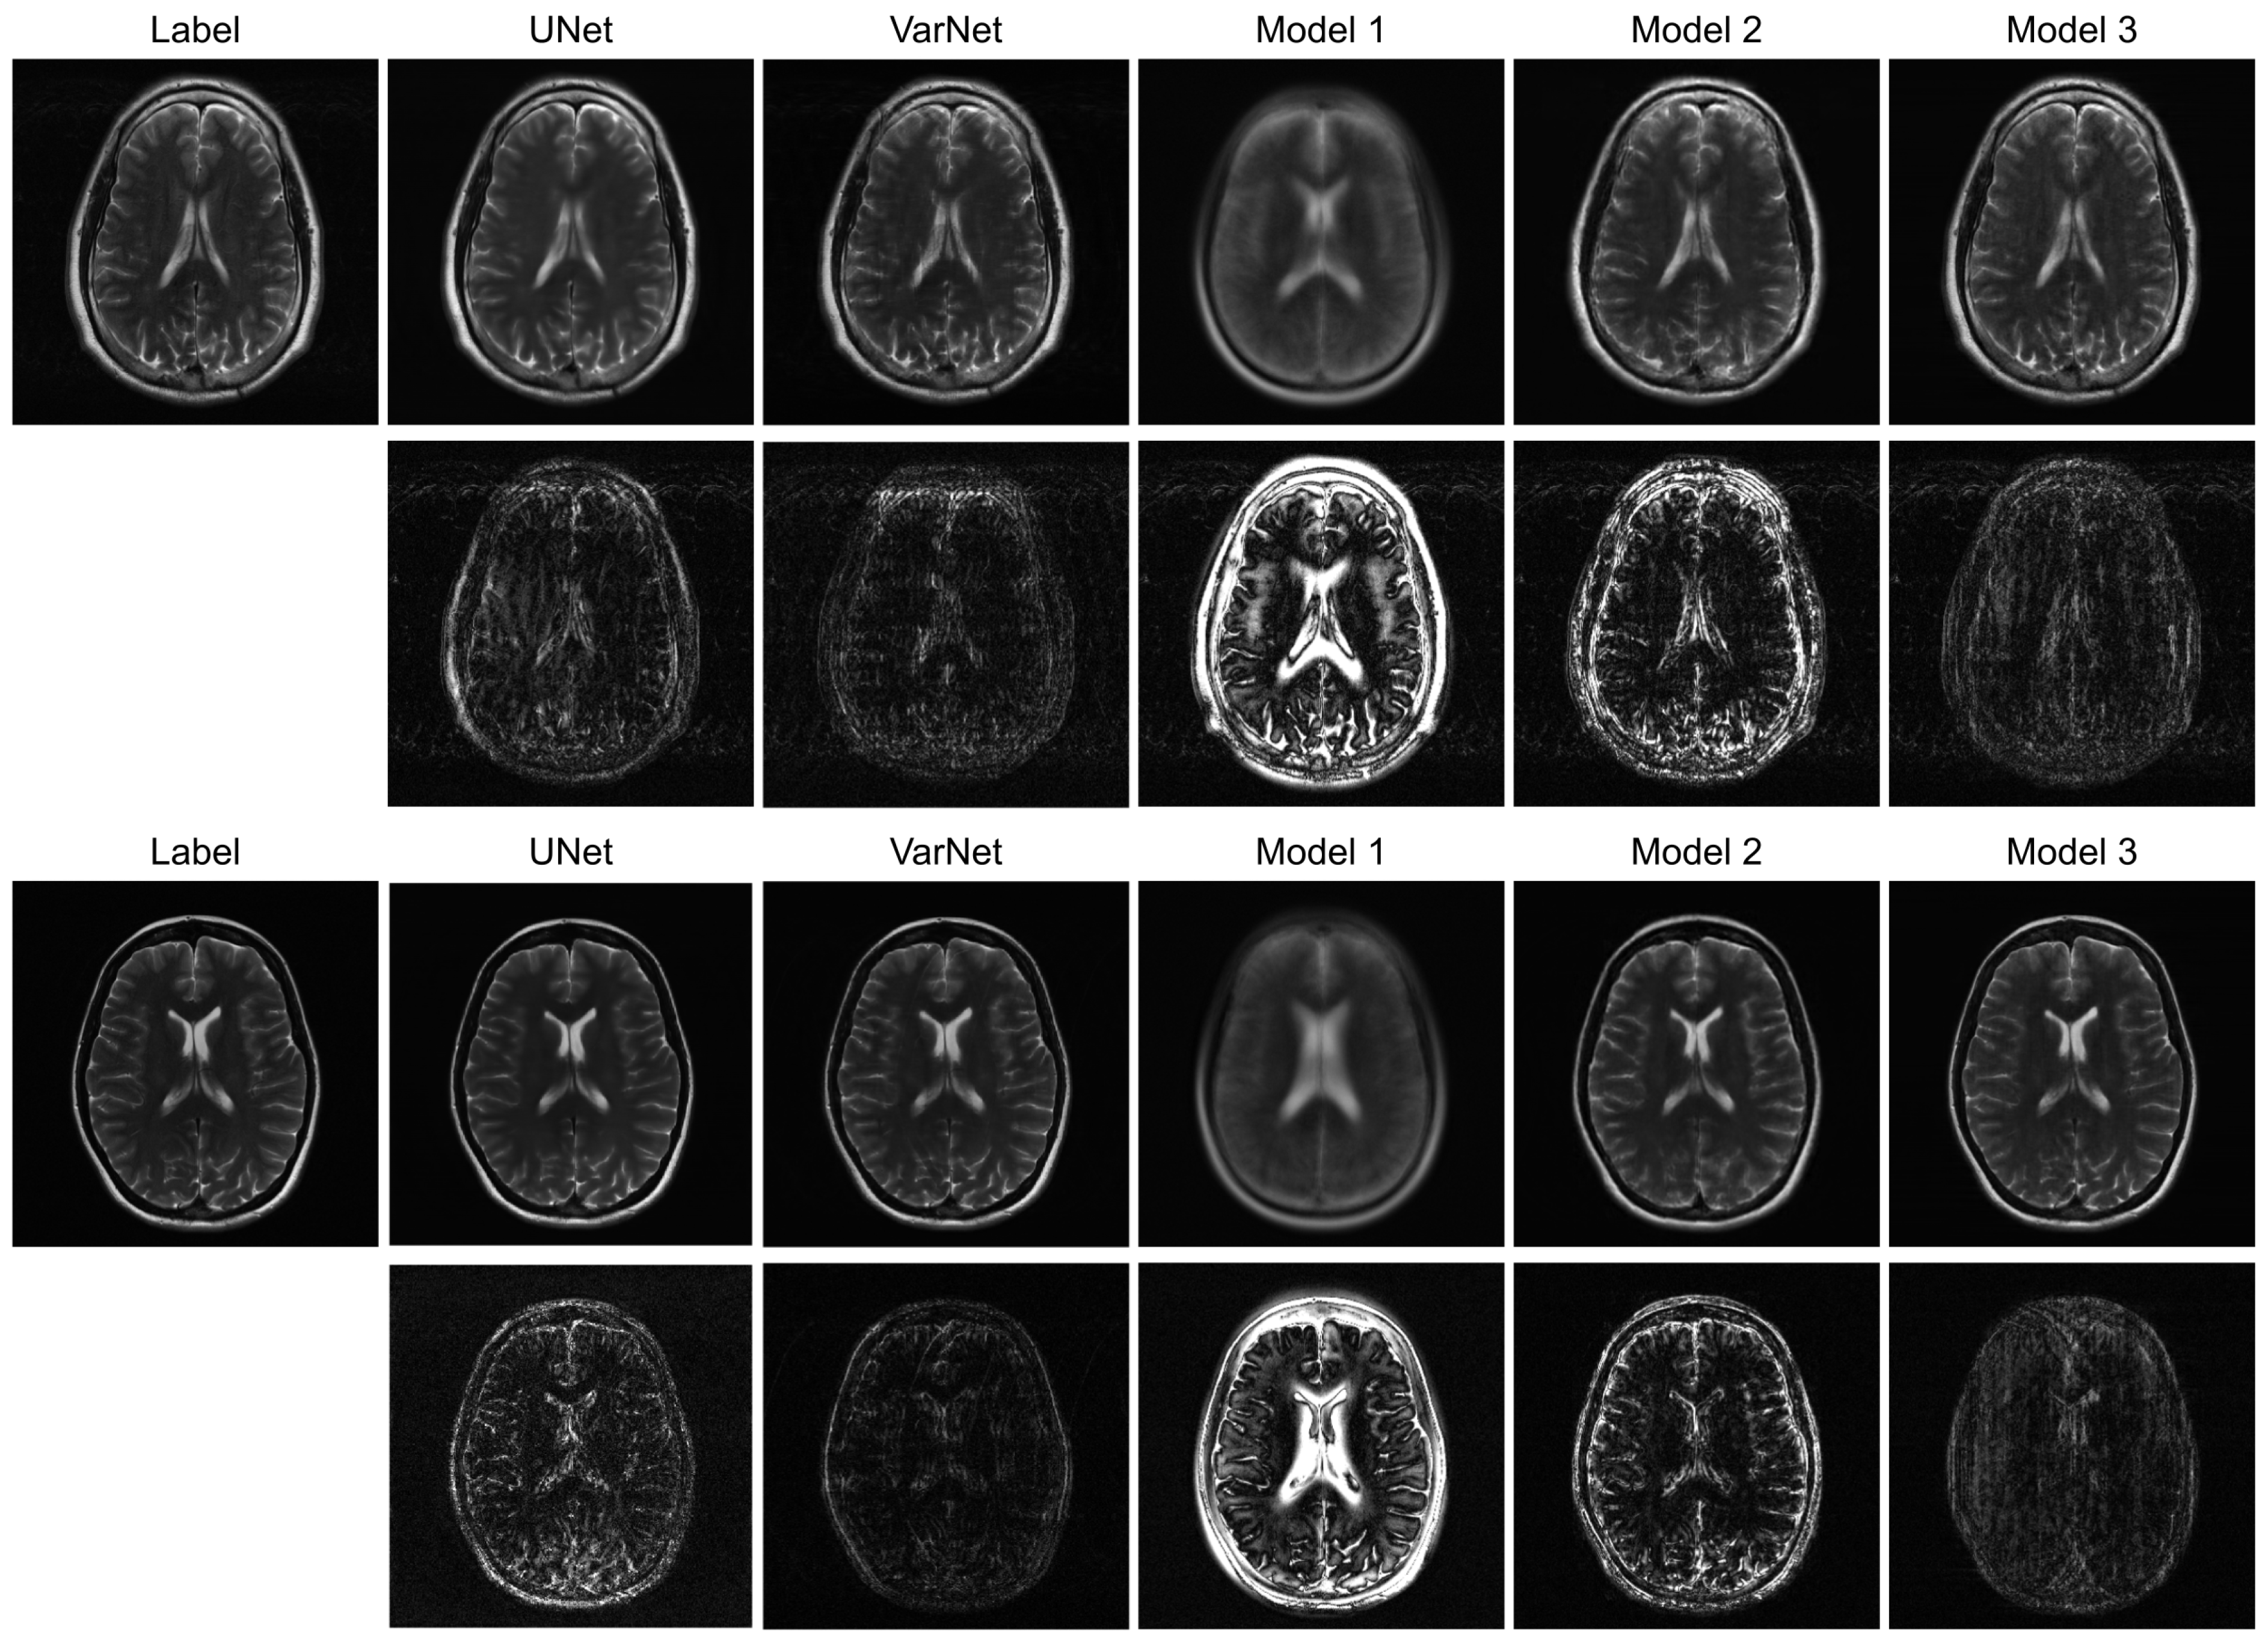

Figure 3 illustrates sample images and the corresponding error maps from Models 1–3, UNet, and VarNet for the R = 4 regular sampling pattern. The first column shows the reference (label) images, while columns 2–6 show the reconstructed images and the corresponding error maps (10× amplification) from UNet, VarNet, and Models 1, 2, and 3, respectively. Table 1 provides the quantitative results for the R = 4 regular sampling pattern.

A qualitative visual assessment of the reconstructed images in Figure 3 reveals significant performance differences among the models. The proposed Model 3 demonstrates exceptional reconstruction quality, achieving high fidelity to the reference image that is visually comparable to the performance of the UNet. Furthermore, the proposed model exhibits competitive performance against VarNet. As shown in Table 1, Model 3 achieves higher SSIM and VIF compared to VarNet, indicating superior perceptual quality and structural fidelity. The error map for Model 3 shows minimal structural error and low residual noise, indicating a successful recovery of fine anatomical details. In contrast, Model 1, which simply utilizes a final MLP for reconstruction, fails to capture essential anatomical structures, resulting in a severely blurred image with a high degree of structured error, as evidenced by its error map. Model 2, which employs a Transformer-based decoder, shows a substantial improvement over Model 1 by reconstructing the overall brain morphology. However, its error map contains more noticeable residual artifacts and noise compared to Model 3, suggesting a less complete removal of aliasing effects.

Figure 3. Reconstructed images and corresponding error maps for ViT-based models, UNet, and VarNet (intensity of the error maps is amplified by 10).